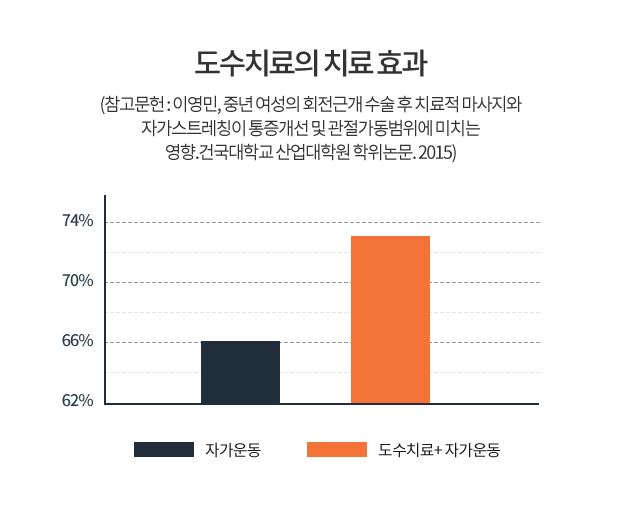

자가운동만으로의 한계를 전문재활치료로

빠른 통증의 개선 및 기능회복을 시행합니다.

Q. 콕의 도수치료 정말 효과가 있나요?

A. “많은 분들이 콕의 도수치료를 경험하셨습니다.”